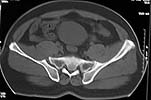

Middle aged male who was injured when a log of wood fell on him ina saw mill. Haemodynamically patient stable. No visceral injuries detected. The following musculoskeletal injuries detected: 1) Closed fracture femur. 2) Pubic symphysis disruption. 3) Right inf pubic rami fracture. 4) Right acetabular fracture. Head of femur located. 5) Right Sacroiliac joint anterior opening.

Your plan sounds fine. The acetabular fracture looks like a high ramus fracture that happens to enter the acetabulum. The CT scan is blurry, and you haven't provided any oblique views of the acetabulum - but my guess is that the 'tab is concentric.